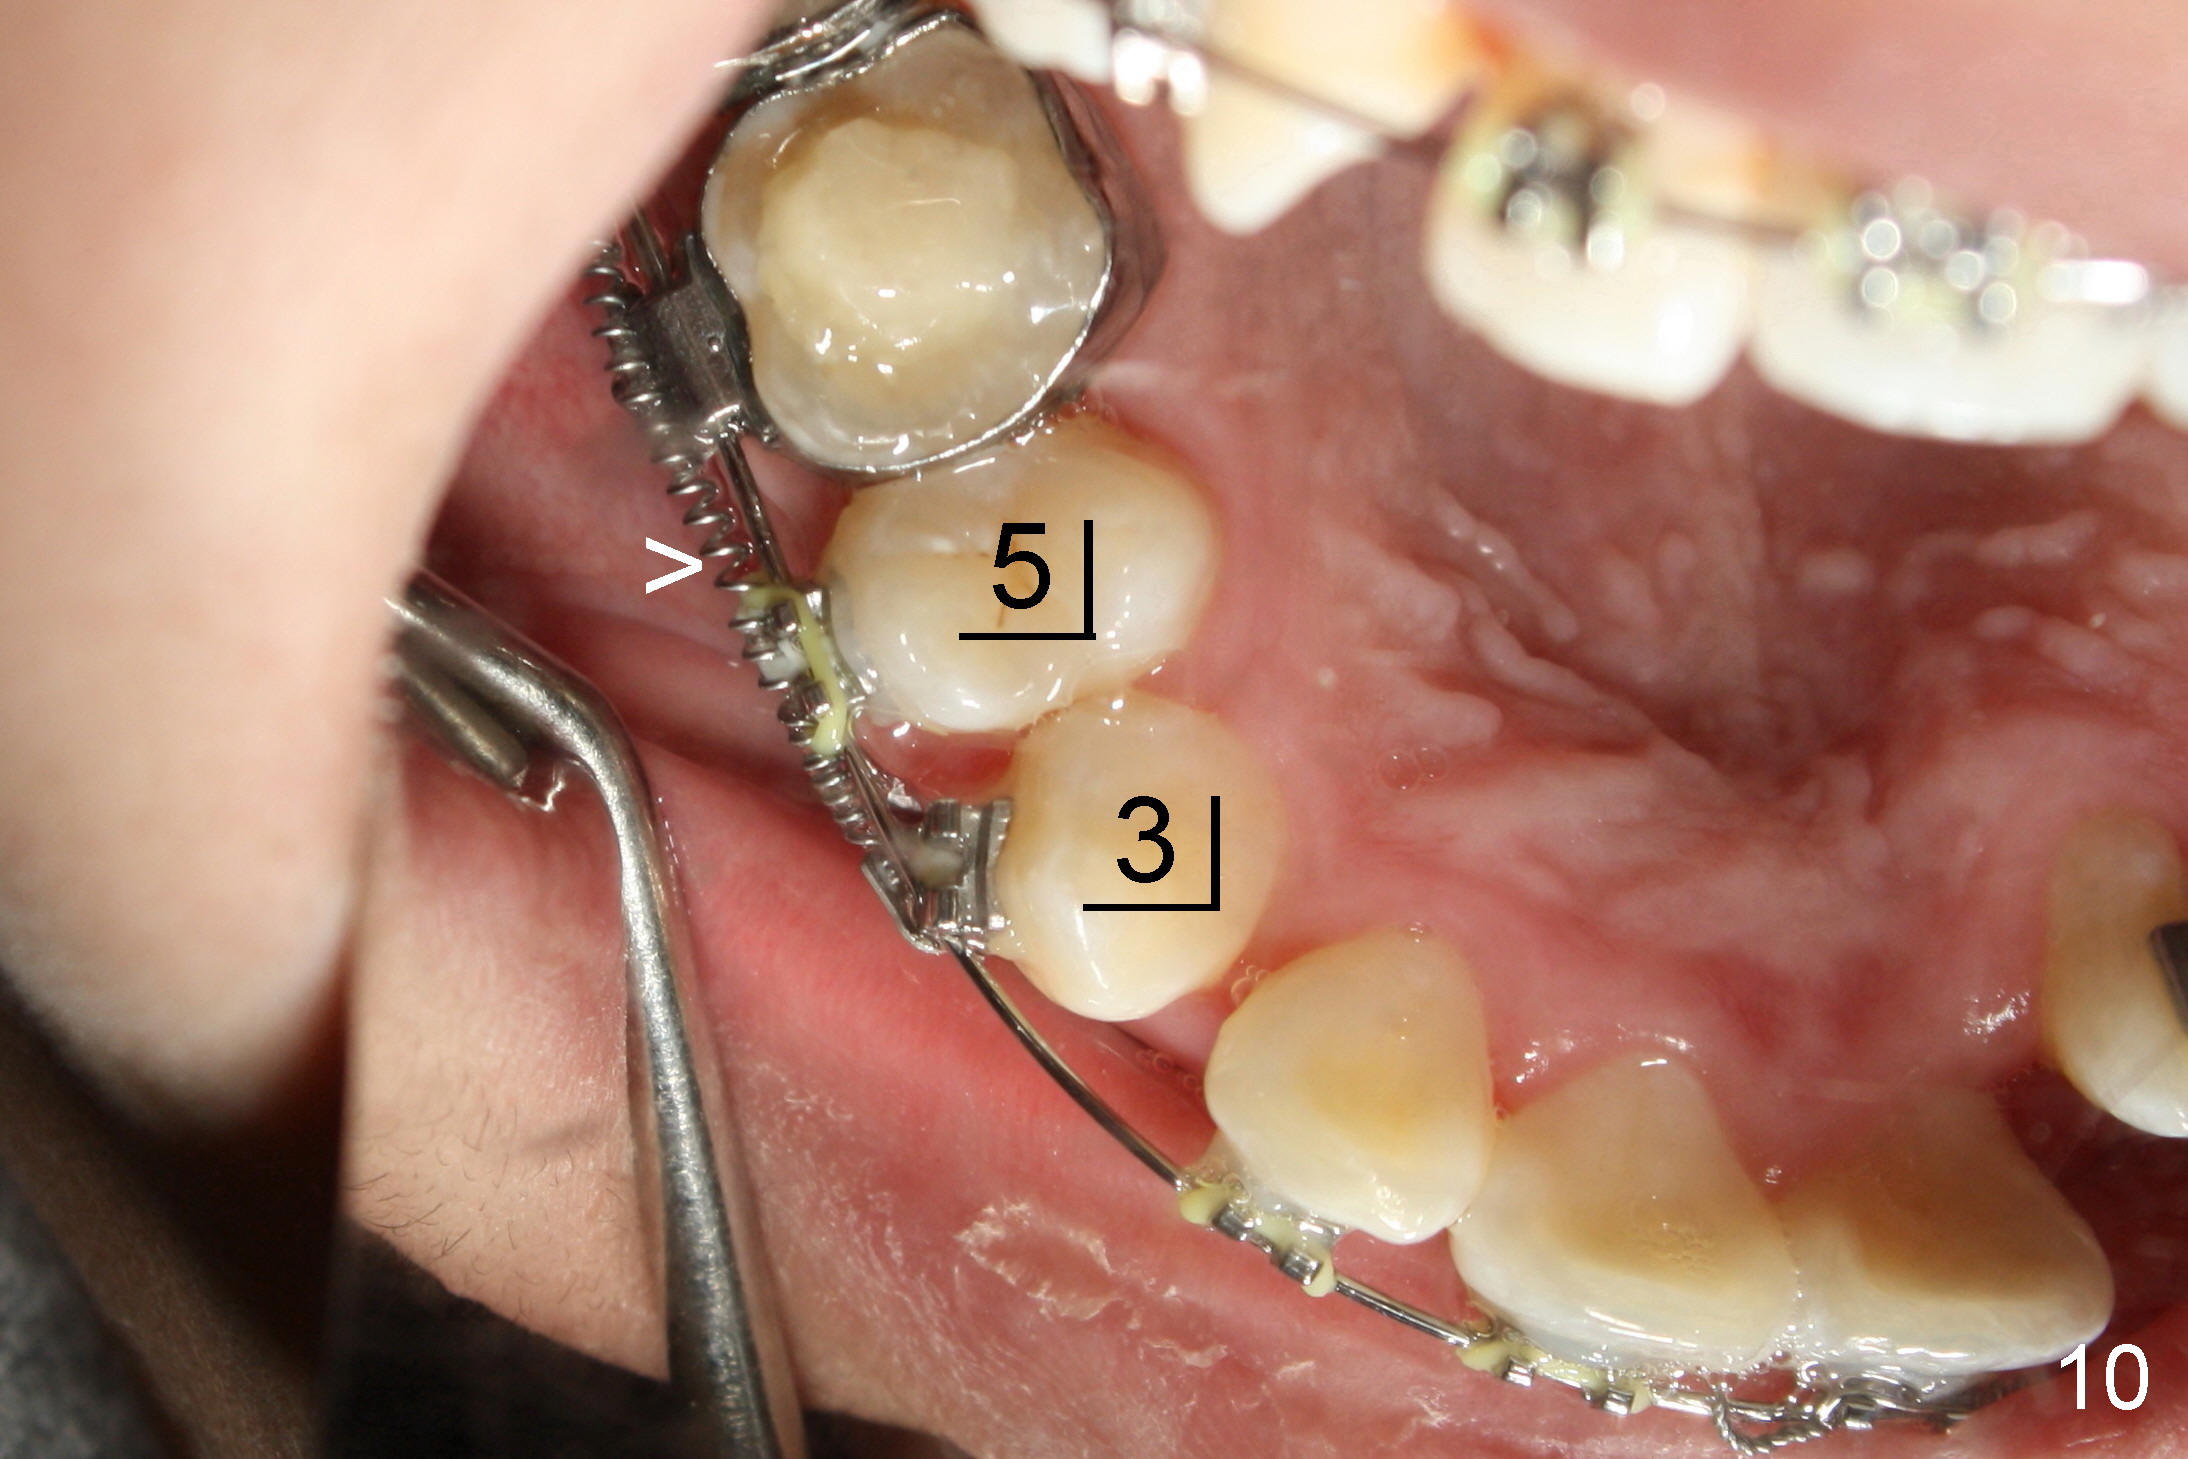

One month of closed coil spring (150 gms-9mm) (Fig.10 >, mirror image) results in the closure of the space between UR3 and 5. At the same appointment, there is enough space for UL 2 (Fig.11, mirror image). Notice the rotation of UR 3 due to retraction of the closed coil spring (Fig.10). It is immediately corrected when a rotation wedge is placed on the mesial of UR3 (Fig.12 *). However, there is an instant separation of UR 3 and 5. The closed coil spring has to be used (Fig.12>).